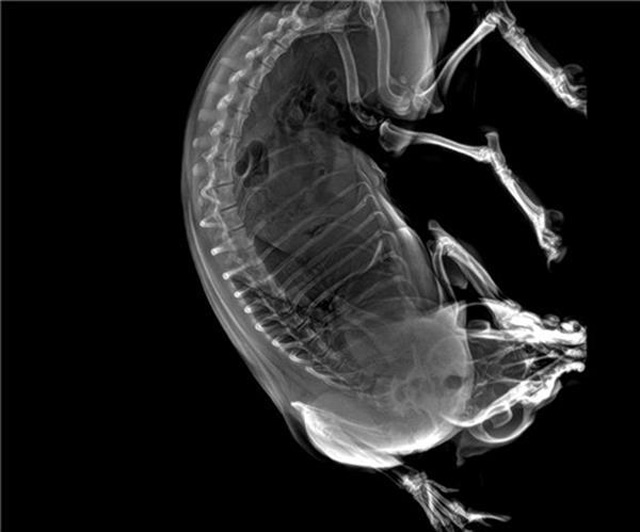

寵物DR的工作原理是X光線穿透動(dòng)物體后在屏幕或者膠片上面顯示體內(nèi)影像。輔助寵物醫(yī)生讀片跟準(zhǔn)確的治療,寵物DR顯示是寵物醫(yī)院診所的配置,提高了診斷的效率。DR的檢測(cè)效率比X線高44%,成像快采集時(shí)間10MS以下。3秒左右就可以看到檢查圖像。常規(guī)的胸部DR還要幾分鐘。所以寵物DR的出片速度是非??斓?。很高的空間分辨率低噪音??梢垣@得高清圖像,提高檢測(cè)正確率避免誤診等等問(wèn)題。數(shù)字化圖像的優(yōu)勢(shì)是可以保留原始數(shù)據(jù),圖片識(shí)別,二三維的重建,醫(yī)學(xué)影像學(xué)實(shí)現(xiàn)全數(shù)字化和無(wú)膠片化鋪平了道路。提供照片打印服務(wù),防止照片丟失而重復(fù)照片。有針對(duì)性的對(duì)圖像進(jìn)行處理,以提高診斷率。寵物DR的輻射量很低的,對(duì)人體的輻射風(fēng)險(xiǎn)不大。